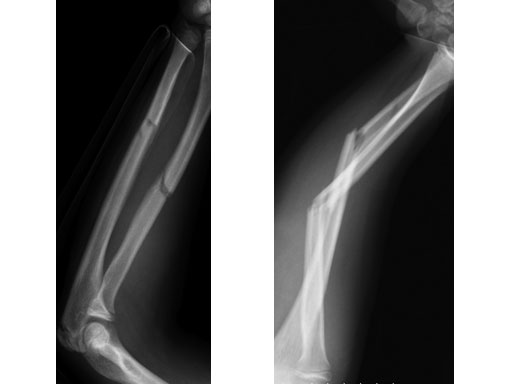

Case 1: Transverse forearm, shaft fracture (22D/4.1), 9-year-old girl.

Case provided by Theddy Slongo, Bern, Switzerland